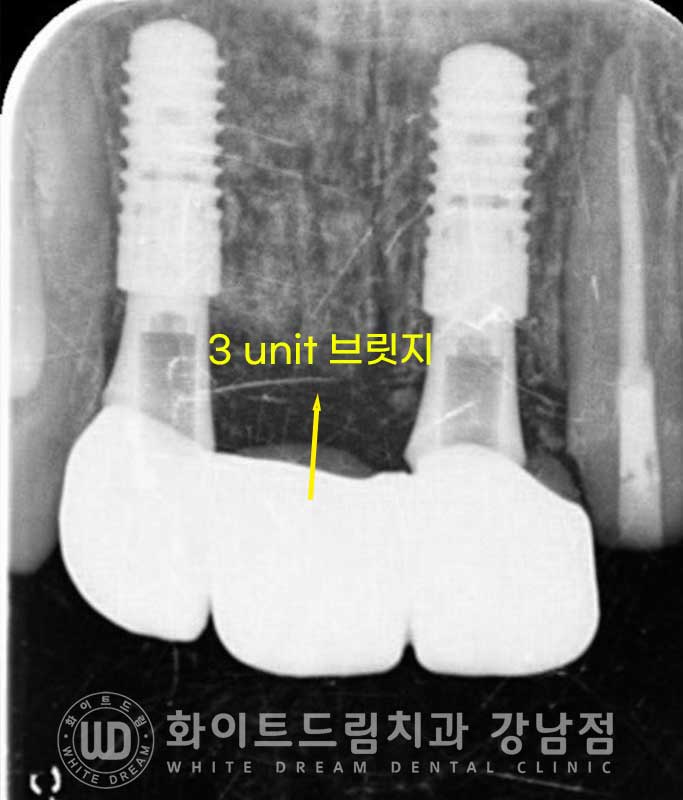

▲ 앞니 빠짐 임플란트 식립 / 24.04.13

환자분은 치아가 빠진 12, 21번 자리에 임플란트를 식립하고

흡수된 골폭은 뼈이식을 동반하여

심미적으로 잇몸이 풍성해 보일 수 있도록 처치하기로 했습니다.

그 후 3unit 지르코니아 브릿지 보철을 세팅하기로 했으며

▲ 임플란트 식립 후 신경치료 진행

환자분은 식립 후 4개월의 회복 기간을 가졌고

원내에서 제작된 임플란트 브릿지와 22번 크라운 동시 세팅했습니다.